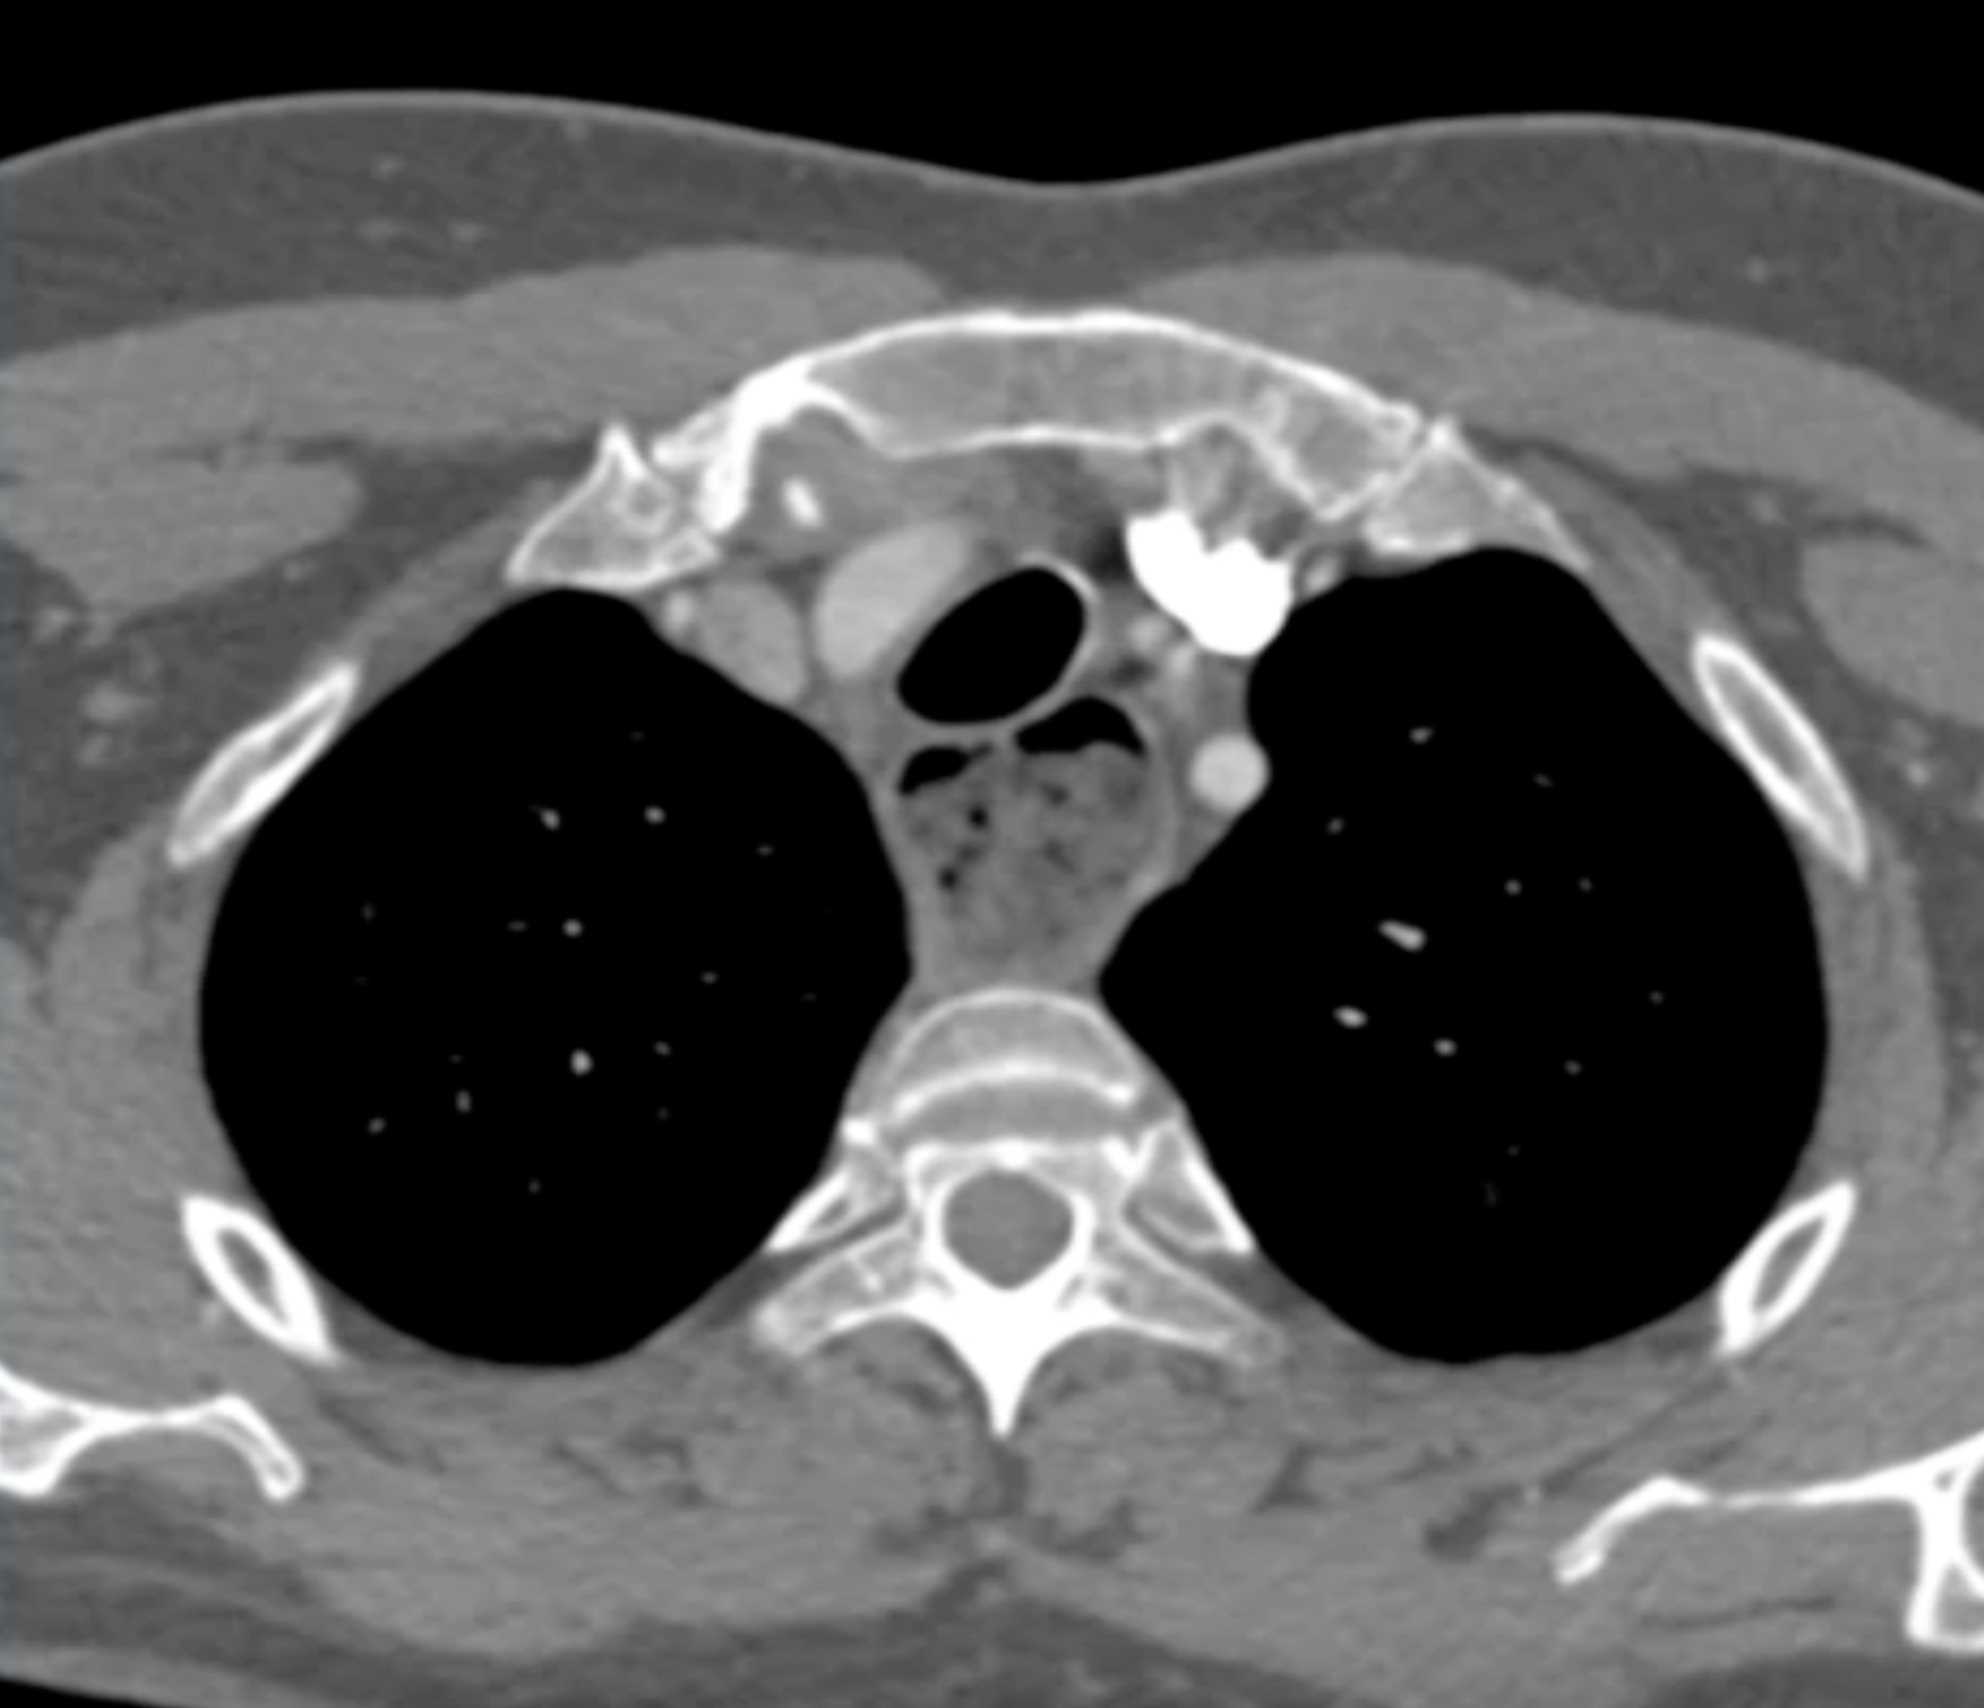

Thymic Carcinoma